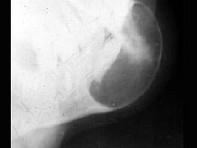

- 单项选择题女,40岁, 下颌颏部隆起,结合图像最可能诊断 ( )

A、造釉细胞瘤

B、骨软骨瘤

C、含牙囊肿

D、骨巨细胞瘤

E、动脉瘤样骨囊肿